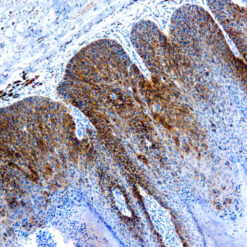

CD79a Antigen (HM47/A9)

This antibody is specific to human CD79a antigen complex, consisting of two polypeptides non-covalently associated with membrane-bound immunoglobulins on B cells. This complex of polypeptide and immunoglobulins constitute the B cell antigen receptor. The two components of this complex are designated CD79a and CD79b. The CD79a antigen appears at the pre-B cell stage, early in maturation and persists until the plasma cell stage. The CD79a antigen is found in majority of acute leukemias of precursor B cell type, in B cell lines and B cell lymphomas.

| Positive Control Tissue | Tonsil |